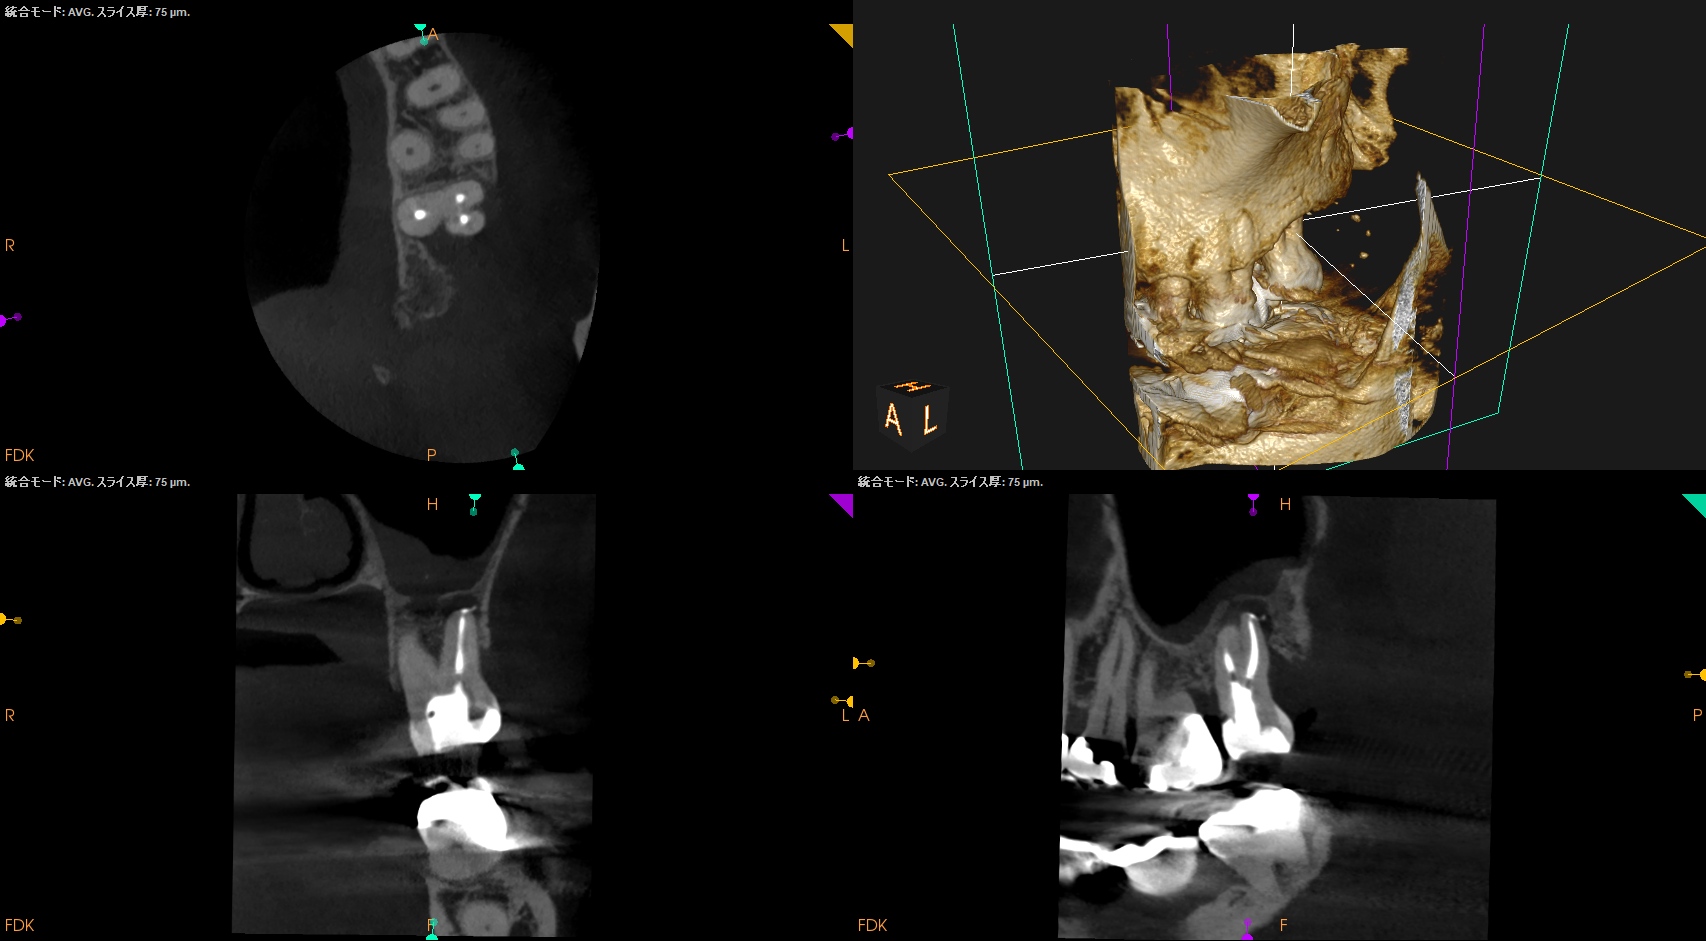

#15 RCT(2024.7.31)

術後にPA, CBCTを撮影した。

MB

DB

P